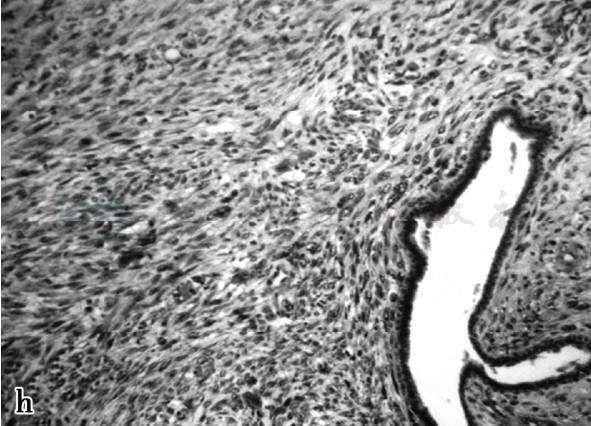

图5 图5h,间质呈明显的肉瘤样特征,通常表现为纤维肉瘤改变肿(见文后彩图)

诊断:病例2,恶性叶状肿瘤